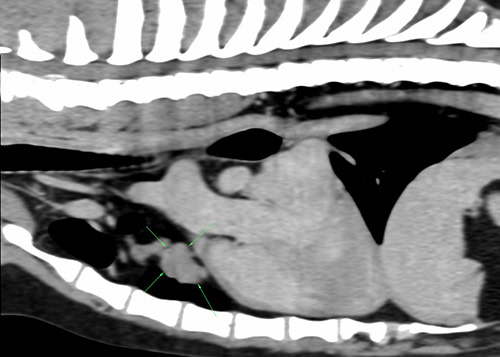

Tommy is a 9 year old Labrador who was seen by our orthopaedic service for investigation of severe elbow pain. Part of these investigations involved CT scans performed which when reviewed by our imaging team diagnosed both severe elbow dysplasia (the cause of the lameness) and a surprise mediastinal mass. This mass then sampled under ultrasound guidance and diagnosed as a thymoma.

After discussion with our internal medicine team, surgical removal of the thymoma was recommended to the owners. The mass was small enough (3cm) to be removed by thoracoscopy (“key-hole” chest surgery) and so this was planned by our Soft Tissue team. Tommy was then anaesthetised and put onto single-lung ventilation by our anaesthesia team so that there was enough room within the chest for the surgeons to safely remove the mass. The tumour was completely removed and Tommy recovered very smoothly in our ICU department staffed by our ECC (emergency and critical care) team. Tommy was very bright and comfortable the day after surgery and was discharged that afternoon. Tommy went on to recover uneventfully from his surgery and is currently doing very well. Not only does he no longer have a tumour growing in his chest but his original lameness has resolved and he is out enjoying his walks again!